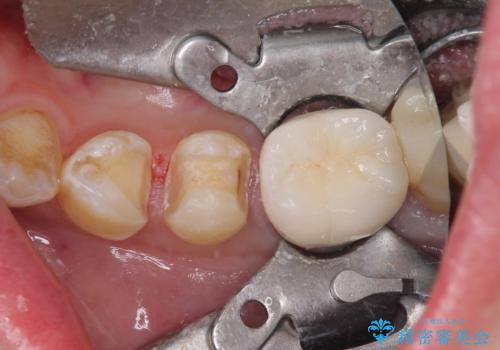

診査を行った結果、第一小臼歯にある樹脂の詰め物(コンポジットレジン)と歯の境目が痛みの原因であることが分かりました。

また、隣接する第二小臼歯も虫歯になっていることも分かったため、2歯を同時に治療するにしました。

下顎の目立つ位置であるため、セラミックインレーによる修復治療を行うこととしました。